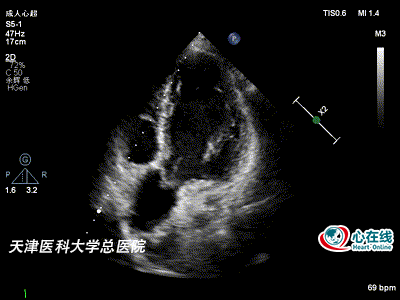

二维心尖五腔心切面示,主动脉瓣心室面可见一细长的条带状中等回声